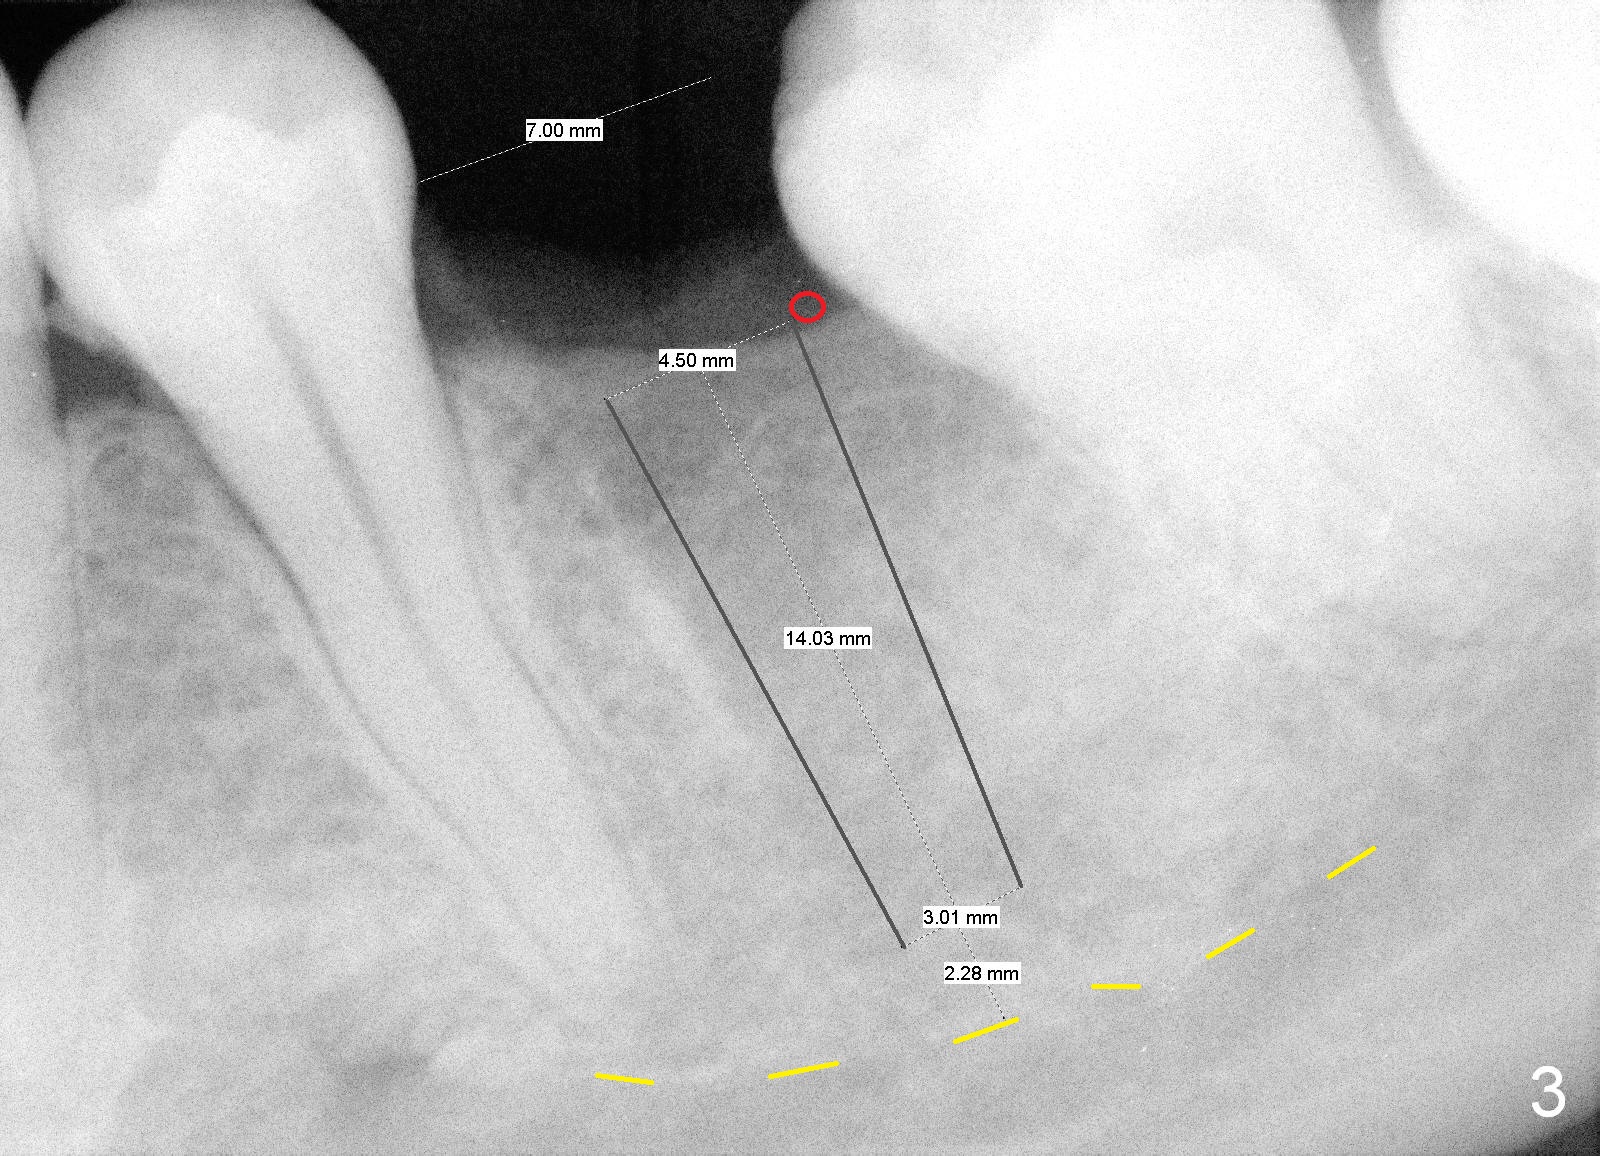

A 29-year-old man presented for #19 extraction a year ago (Fig.1). Probably due to long-termed loss of the distal portion of the crown of #19 (*), the tooth #18 has undergone mesial tilting (arrow). Now he returns requesting implant, but the tilting is worse (Fig.2 double arrows). What X-ray cannot show is severe atrophy buccolingually, increasing difficulty in implant placement. A much smaller implant can be placed (Fig.3), as compared to an immediate implant.

Reamers are used for osteotomy and saving the autogenous bone with control of depth. Bone graft is most likely placed buccodistally (Fig.3 red circle). To prepare the recipient site (decortication), surgical handpiece is needed. Long-termed resorption membrane is cut to cover the graft.